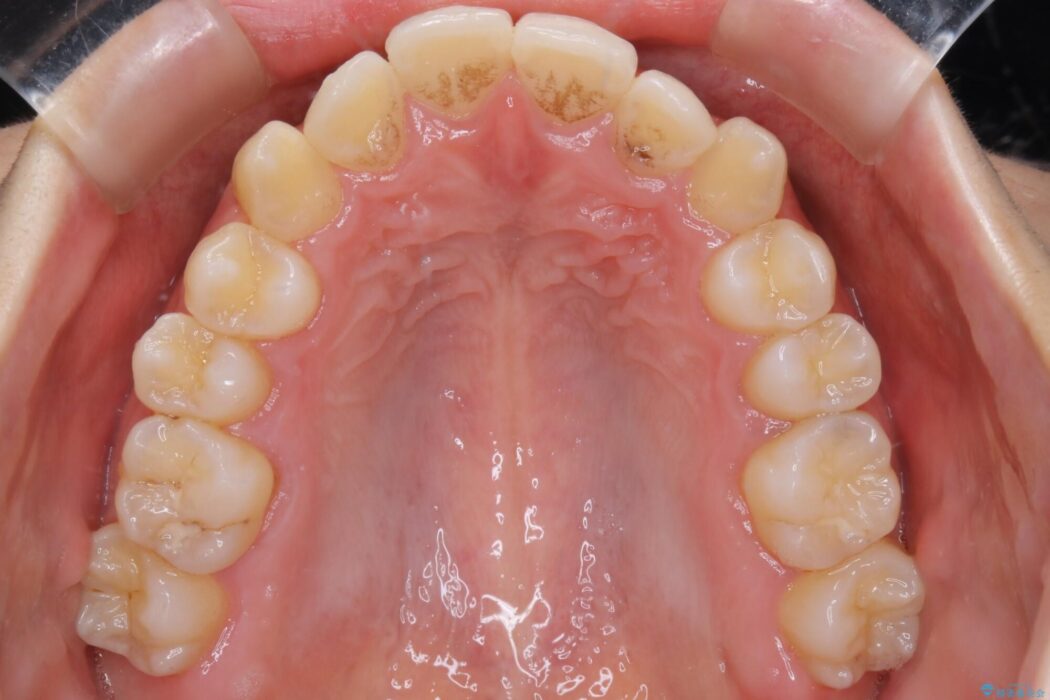

検査したところ叢生度合いから抜歯をせずとも治療が可能と判断しましたので、インビザラインでの非抜歯矯正を行う方針としました。